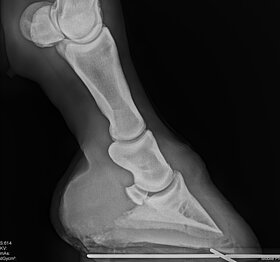

Röntgen-Equipment

Mit akkubetriebenen Röntgengeräten können wir bei orthopädischen Untersuchungen oder Verletzungen (auch auf der Koppel oder an einem Offenstall) ohne Strom direkt vor Ort röntgen und die Bilder gleich auswerten.